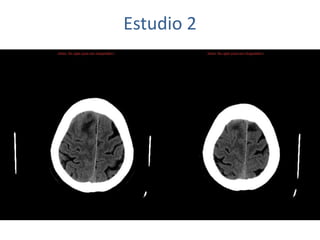

Estudio 2

• Estudio sin y con contraste, con reconstrucciones sagitales y coronales

del estudio con contraste.

Se observa una lesión ocupante de espacio en lóbulo frontal derecho que

presenta un tamaño de 18 x 32 x 22 mm (cc x ap x tr), bilobulada, no del

todo bien delimitada, con realce en anillo irregular, con hipocaptación

central, probablemente por necrosis, y asociada a un extenso edema

vasogénico con efecto masa tanto sobre los surcos de la convexidad

como sobre la cisterna insular, el sistema ventricular y la línea media,

esta última con un desplazamiento de 5 mm a la altura del septo

interventricular.

No se aprecian otras lesiones focales intra o extraaxiales de significación

patológica.

Habría que considerar como primera posibilidad que se tratase de una

lesión metastásica, por bien un tumor primario, aunque no se puede

descartar otras opciones, sin imprescindible correlación con la clínica y

con sus antecedentes.